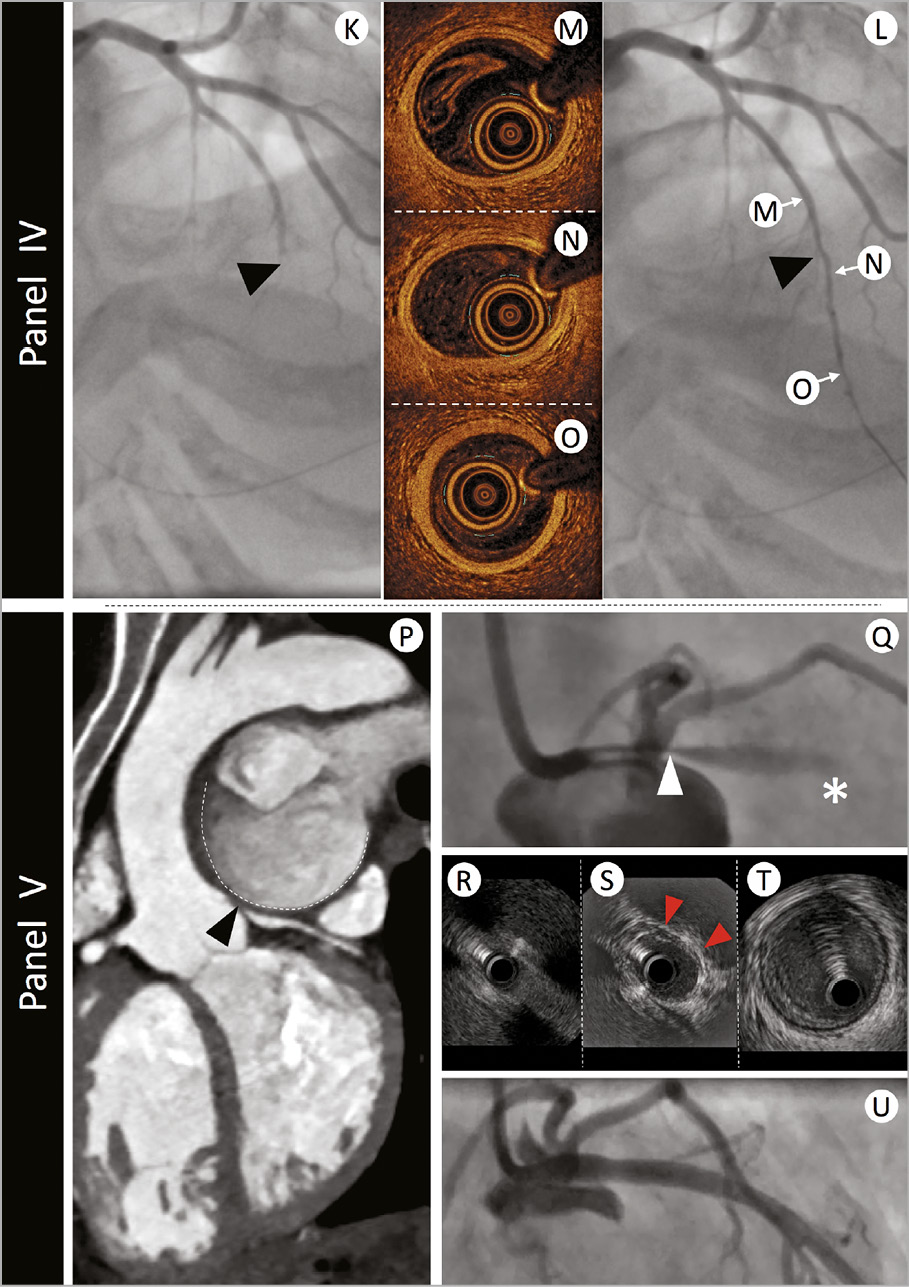

A study of women presenting with myocardial infarction (MI) and non-obstructed coronaries revealed plaque disruption in 38% of those undergoing IVUS evaluation.32 Additionally, the superior resolution of OCT has the potential to detect a thromboembolic or vasospastic aetiology, if thrombus is observed in the absence of atherosclerosis or luminal irregularity (Figure 4). Clearly, the differentiation between a plaque-induced event and the presence of embolic thrombus, despite angiographically non-obstructed coronary arteries, significantly alters the acute and long-term patient management. Consequently, we advocate undertaking intracoronary imaging at the time of index angiography, if there are non-obstructive coronary lesions or if the clinical presentation does not favour other noncoronary MINOCA aetiologies (e.g. myocarditis). Usually imaging will be limited to epicardial territories with coronary lesions or associated ECG/echo features of ischaemia, however, three-vessel imaging may be considered (Figure 1).

Figure 4. The role of intravascular imaging in non-atherosclerotic acute coronary syndrome presentations. Panel I: a 39-year-old man with no cardiovascular risk factors presented with acute onset chest and abdominal pain and evidence of inferior ST elevation. Immediate angiography demonstrated a filling defect in Segment 3 of the right coronary artery (Panel I-A - filling defect highlighted in enlarged panel by white dotted outline).Optical coherence tomography assessment confirmed fresh red thrombus with associated attenuation [Panel I-B - red dotted lines indicate margins of attenuation (white double arrow head arc)]. Neighbouring regions demonstrated minimal pathological intimal thickening with a tail of thrombus (Panel I-C - red dotted outline). The patient was commenced on a glycoprotein 2b/3a inhibitor and symptoms settled. Further evaluation of his abdominal pain revealed acute ischaemia of his small bowel secondary to thrombotic occlusion. Panel II: a 44-year-old man with history of childhood Kawasaki disease with coronary involvement presented with stable symptoms of angina and underwent investigation by coronary angiography. Panel II-D demonstrates proximal aneurysmal disease of the left anterior descending artery. Intravascular ultrasound evaluation (Panel II-E) highlights a large aneurysm 7 mm in diameter with minimal evidence of atheroma. The size of the aneurysm prevented accurate assessment by optical coherence tomography (Panel II-F). Panel III: A 39-year-old woman with a history of hypertension presented with acute onset chest pain, minor troponin elevation, and dynamic anterior t wave changes on her electrocardiogram. Angiographic assessment (Panel III-G) revealed mild-moderate calibre reduction in the mid-left anterior descending artery. Optical coherence tomography was undertaken to better delineate the nature of her angiographic abnormalities. Panel III-H demonstrates evidence of intima-medial detachment with intra-mural haematoma (red arrowheads) in a segment of the proximal left anterior descending artery that appeared angiographically normal. More extensive intramural haematoma with reduction in lumen calibre was evident at the level of the angiographic stenosis (Panel III-I). Optical coherence tomography analysis of the distal left anterior descending artery segment confirmed normal vessel architecture (Panel III-J). The patient was treated conservatively and made an excellent recovery. Panel IV: a 42-year-old woman without cardiovascular risk factors presented with acute onset chest pain and evidence of anterior ST elevation. Immediate angiographic assessment (Panel IV-K) revealed mid-vessel occlusion of the left anterior descending artery (black arrowhead). Passage of an 0.014” interventional guidewire resulted in recanalization of the vessel (Panel IV-L) and resolution of the ECG changes. Optical coherence tomography evaluation was undertaken to better delineate the aetiology of presentation. No significant vessel abnormalities were detected proximal (Panel IV-M), at the level of occlusion (Panel IV-N), or in the distal vessel segment (Panel IV-O). Panel V: a 47-year-old woman with secundumatrial septal defect and Eisenmenger’s syndrome presented to an emergency department with rapidly worsening dyspnoea and palpitations. Electrocardiogram demonstrated sinus rhythm, normal repolarization, and multiple polymorphic ventricular extrasystoles. The echocardiogram showed normal left ventricle ejection fraction with only mild hypokinesia of the mid and distal anterior left ventricular wall. Immediate double rule-out computed tomography scan (Panel V-P) demonstrated extrinsic compression of the LMS (black arrowhead) from a giant pulmonary artery aneurysm (contour outlined with dashed white line). Urgent angiography (Panel V-Q) confirmed a severe ostial stenosis of the left main stem (LMS - white arrowhead) and TIMI-1 flow in the left anterior descending artery (white asterisk). A percutaneous interventional strategy was adopted and intravascular ultrasound evaluation was undertaken to appropriately size the LMS. Intravascular ultrasound confirmed dynamic compression of the LMS with complete occlusion of the ostium (Panel V-R), evidence of extrinsic compression (red arrowheads) in the shaft (Panel V-S), and normal vessel in the distal LMS segment (Panel V-T). The patient proceeded to intravascular ultrasound-guided intervention with an excellent result (Panel V-U).

Spontaneous coronary artery dissection

Spontaneous coronary artery dissection is observed in 2-4% of angiograms undertaken for ACS.38,39,40 In pre-menopausal women <50 years old presenting with STEACS, the angiographic prevalence of SCAD is 10.8%.39 The angiographic characteristics can vary considerably, and a classification system has been proposed.41,42 Type 1 represents the classical linear coronary defect with potential contrast hold-up, however, occurs in <50% cases. Type 2 defects are more commonly observed, either with an abrupt calibre reduction and subsequent normalization (Type 2a) or with persistent calibre reduction to the distal vessel (Type 2b). Spontaneous coronary artery dissection can also mimic coronary atherosclerosis (Type 3 – Figure 4) or simply present with abrupt vessel closure (Type 4). The findings from intravascular imaging studies have increased the interventional community’s awareness of SCAD.43 Intravascular imaging has provided insights into the aetiology, with evidence of separation of the intima and media from the adventitia, with or without communication with the vessel lumen44 and can assist in confirming the diagnosis and guiding treatment.45 However, a significant proportion of SCAD can be diagnosed angiographically, thereby limiting instrumentation of a dissected vessel that carries risks of dissection propagation and vessel closure. Therefore, when possible, a conservative treatment approach to treatment should be adopted when flow is restored.

The recent ESC/ACCA position paper on SCAD supports the role of intravascular imaging where a diagnosis by angiography is uncertain.46 If PCI is deemed necessary due to ongoing ischaemia or clinical instability, it is important to acknowledge that there is an increased risk of procedural complications, consequently imaging may provide important guidance, in particular confirmation of the wire position in true lumen, the longitudinal extent of the vessel disruption and vessel dimensions for stent sizing, which can be problematic angiographically, in the presence of extensive intramural haematoma.

Both IVUS and OCT can be used to facilitate diagnosis of SCAD, and both modalities have strengths and weaknesses. Obvious concerns exist regarding the need for contrast injection to achieve OCT imaging, and we would advise that IVUS is preferred where there is evidence of a false lumen (Type 1), and in small calibre and tortuous vessels, where the imaging probe risks being occlusive. Additionally, the imaging penetration depth of IVUS can be advantageous in proximal vessel dissections, where the false lumen stretches the external elastic lamina, increasing the vessel size. However, IVUS resolution can be insufficient for the detection of intima-media complex fenestrations. Despite the vessel disruption associated with SCAD, OCT can be undertaken, where diagnostic uncertainty exists (typically Types 3 and 4) and provides greater diagnostic clarity than IVUS in assessing the distinctive features of intramural haematoma ± intimal flap46,47 (Figure 1).

Defining aneurysmal or ectatic coronary segments can be challenging angiographically, especially as most recognized definitions require comparison against a ‘normal’ vessel segment.75,76,77 Consequently, recognition of aneurysmal and ectatic disease by adult cardiologists has been frequently overlooked.78 Historical IVUS evaluation of aneurysmal disease highlights the weakness of angiographic interpretation, as only a third of patients had the IVUS appearance of true or pseudo-aneurysmal disease. In the majority of patients the ‘aneurysmal’ segments represent complex plaque or normal vessel neighbouring significant stenoses.79 Therefore, where uncertainty exists it is prudent to consider intravascular imaging to clarify the underlying vessel morphology. In aneurysms exceeding a diameter of ~5 mm, IVUS is the preferred modality due to its depth of penetration, facilitating evaluation of large vessel dimensions (Figure 3).

Kawasaki disease is the best described cause of coronary aneurysm and the leading cause of acquired heart disease in children in developed countries.80 Surveillance of aneurysmal coronary disease is best achieved non-invasively80; however, the incidence of undisclosed aneurysmal disease, discovered at the time of coronary angiography, has a reported rate of 3-5%.78,81 Kawasaki disease patients may present with ischaemic symptoms precipitated by the development of stenoses at the outlet of aneurysms or giant aneurysm thrombosis.82 Intervention in these patients can be challenging due to calcification of the aneurysm and difficulties in assessing the true luminal dimensions,83 and the use of IVUS should be considered to guide intervention.80

Angiographic assessment can also be impacted by the anomalous take-off of the coronary vessels or extrinsic compression. There are many patterns of coronary artery anomaly, however, a ‘malignant course’ at risk of ischaemia or sudden cardiac death is associated with an inter-arterial course (i.e. between the aorta and pulmonary artery).86 Most often these anomalies are discovered incidentally in later life, with increasing frequency now that CT angiography is widely used.87 Occasionally younger patients with syncope or angina may require confirmation of the flow limiting potential of the compressive mechanism.88 IVUS may be useful to confirm extrinsic compression and a slit-like lumen. Coronary compression can also result from dilatation of the pulmonary artery due to pulmonary hypertension,89 acute aortic dissection,90 or following heart surgery91 and invasive imaging may be required to provide diagnostic clarity (Figure 4).